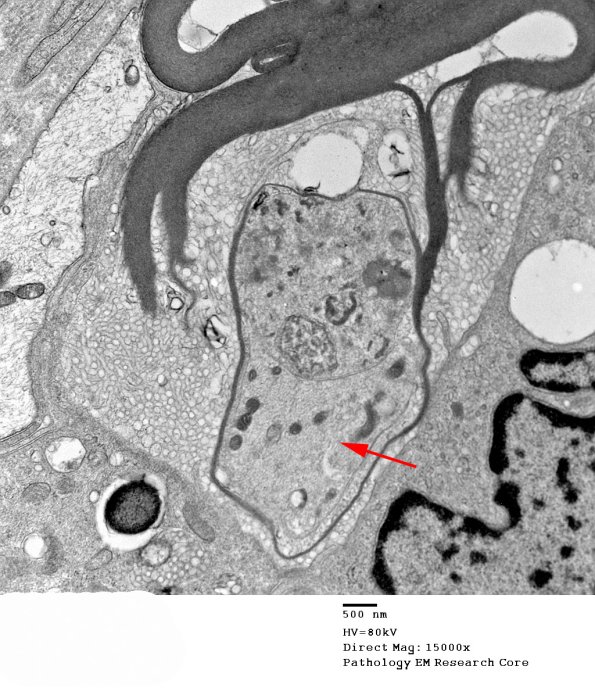

Higher magnification of the remaining myelin sheath and the axon (arrow, 1D1D) which is surrounded by macrophage processes. Notice that the myelin is undergoing vesicular demyelination which represents clear degenerative change in this case as opposed to the artifact we often see resulting from delayed fixation. (electron micrographs)